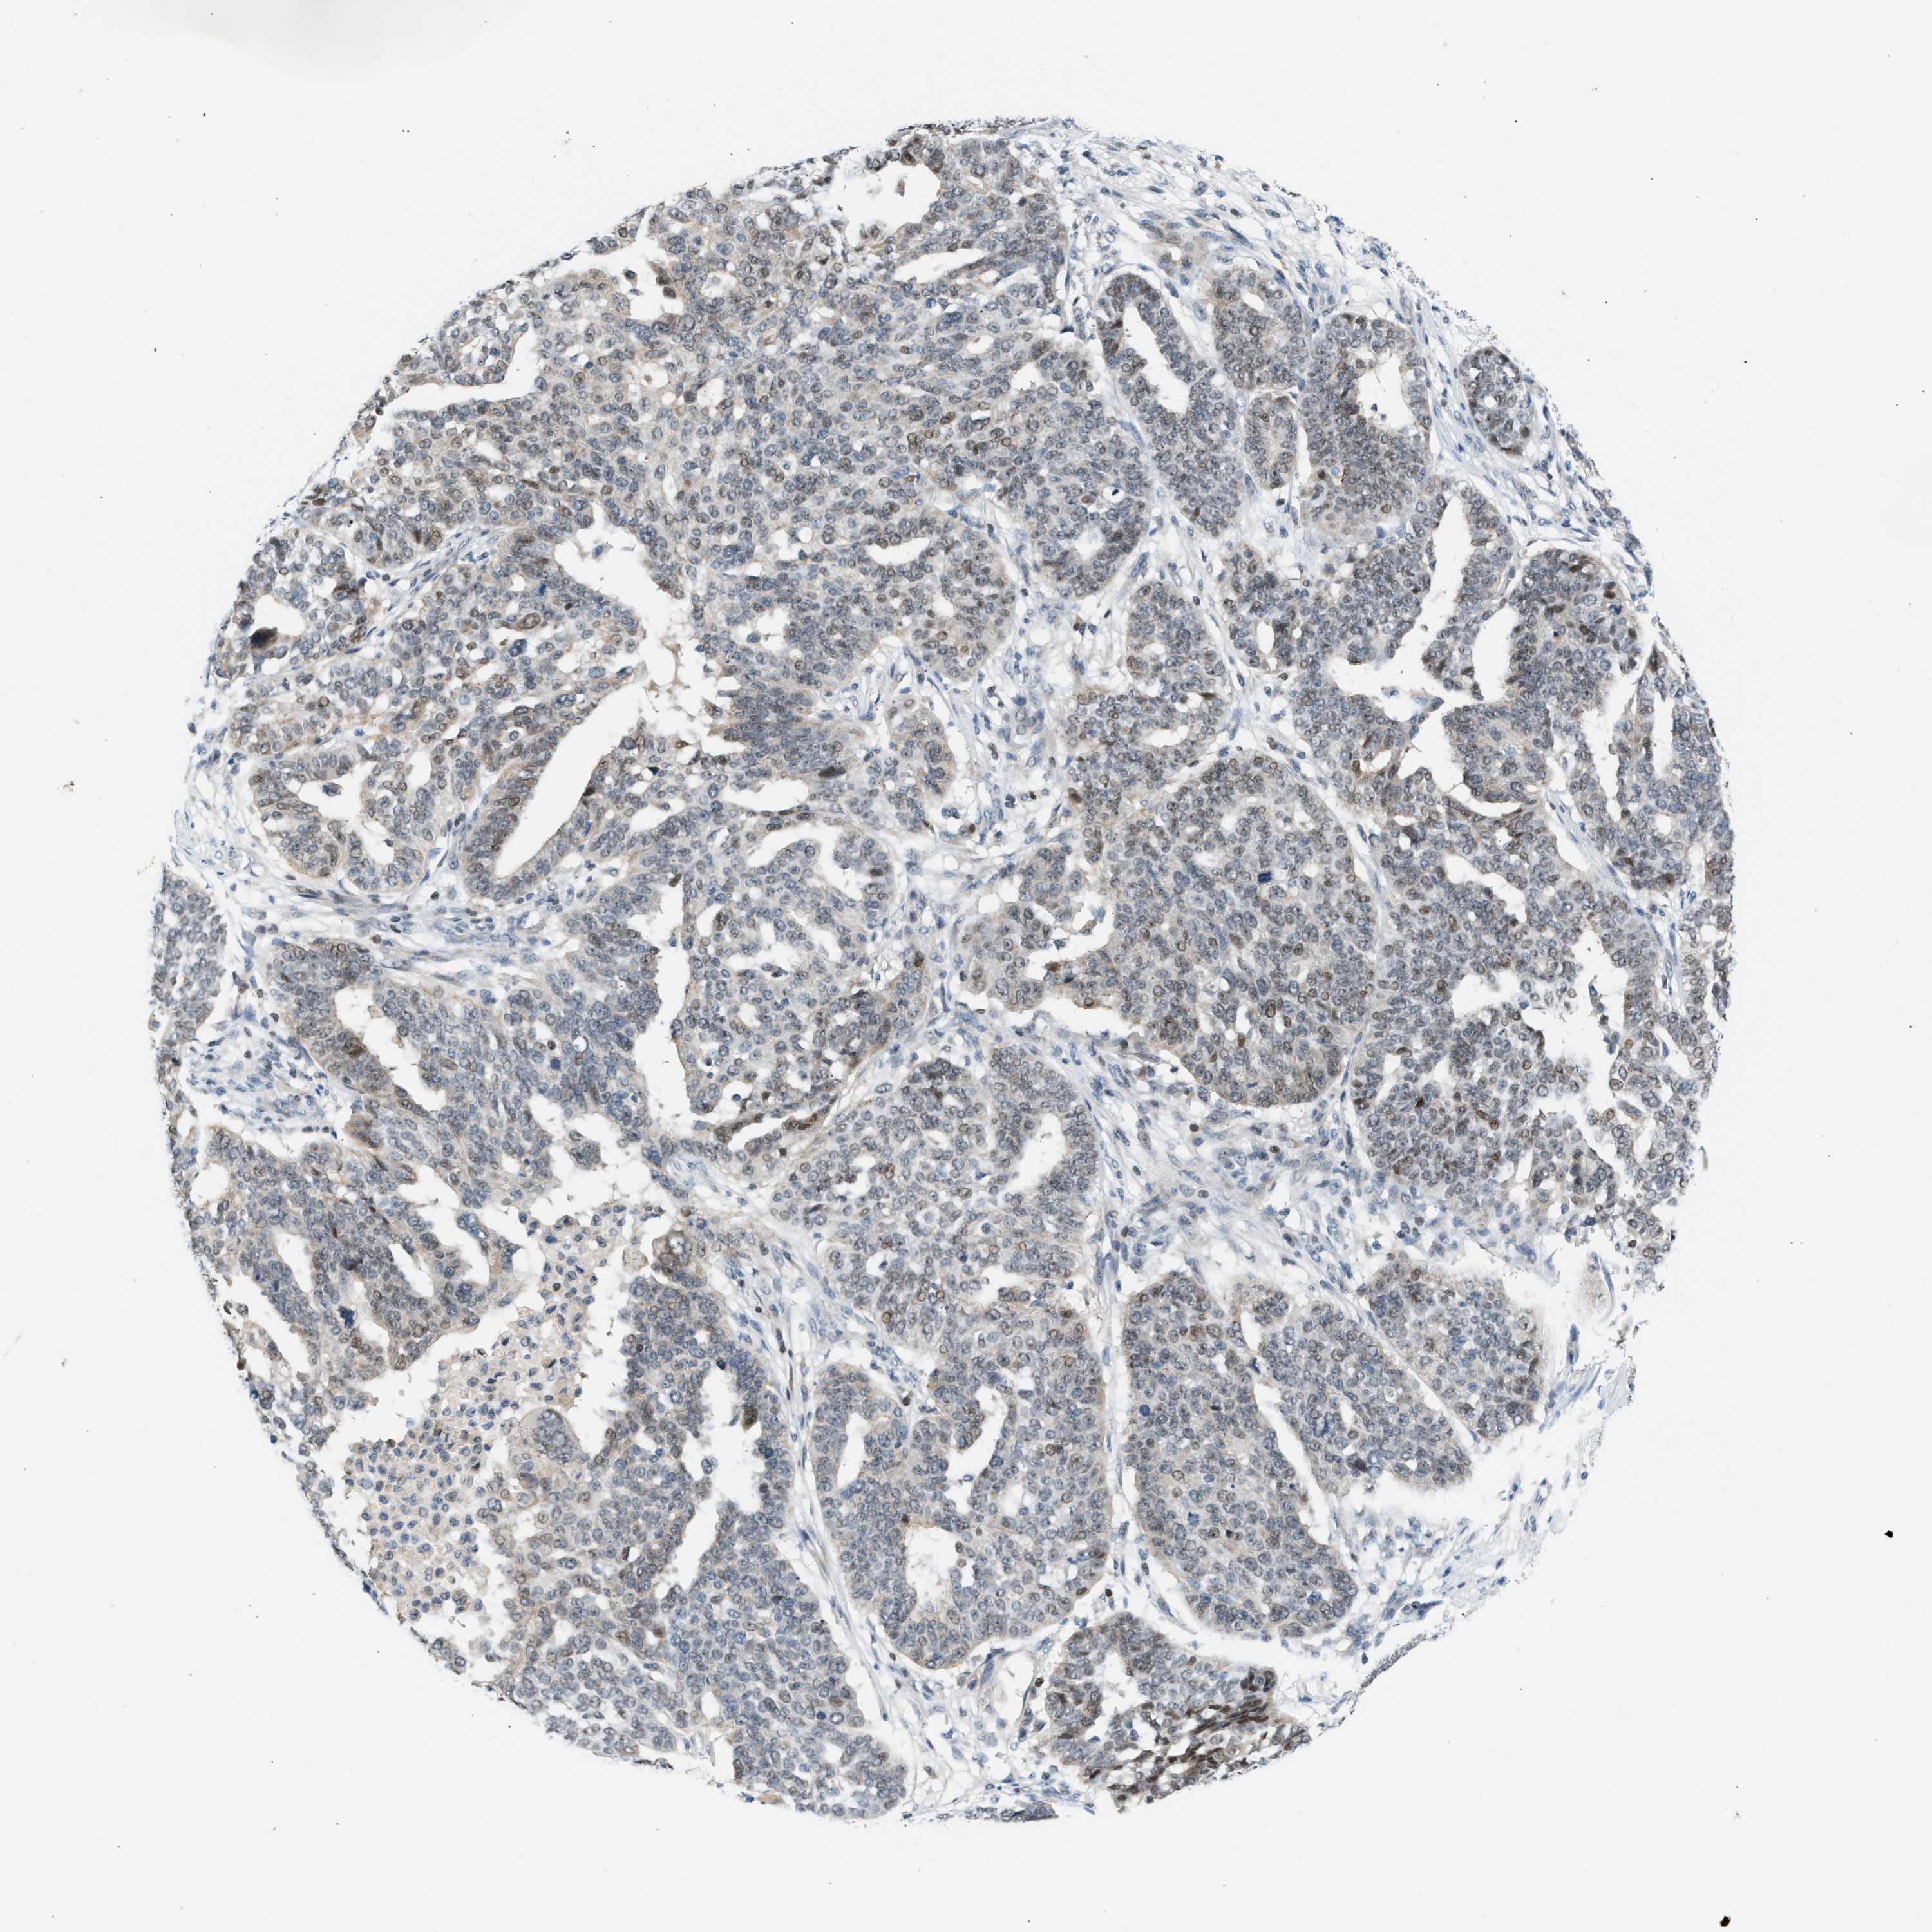

OVARIAN CANCER - Protein expressioni

A mouse-over function shows sample information and annotation data. Click on an image to view it in a full screen mode. Samples can be filtered based on level of antibody staining by selecting one or several of the following categories: high, medium, low and not detected. The assay and annotation is described here.

Note that samples used for immunohistochemistry by the Human Protein Atlas do not correspond to samples in the TCGA dataset.

Antibody stainingi

Antibody staining in the annotated cell types in the current human tissue is reported as not detected, low, medium, or high, based on conventional immunohistochemistry profiling in selected tissues. This score is based on the combination of the staining intensity and fraction of stained cells.

Each image is clickable and will lead to virtual microscopy that enables deeper exploration of all samples and also displays staining intensity scores, fraction scores and subcellular localization as well as patient and tissue information for each sample.

Antibody CAB020139

Staining

High

Medium

Low

Not detected

Intensity

Strong

Moderate

Weak

Negative

Quantity

>75%

75%-25%

<25%

None

Location

Nuclear

Cytoplasmic/membranous

Cytoplasmic/membranous,nuclear

Cystadenocarcinoma, serous, NOS

Carcinoma, endometroid

Cystadenocarcinoma, mucinous, NOS

Carcinoma, NOS